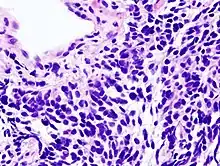

| Micrograph of a small-cell carcinoma of the lung showing cells with nuclear moulding, minimal amount of cytoplasm and stippled chromatin. FNA specimen. Field stain. | |

Small-cell carcinoma is an undifferentiated neoplasm composed of primitive-appearing cells. As the name implies, the cells in small-cell carcinomas are smaller than normal cells, and barely have room for any cytoplasm. Some researchers identify this as a failure in the mechanism that controls the size of the cells.[39]